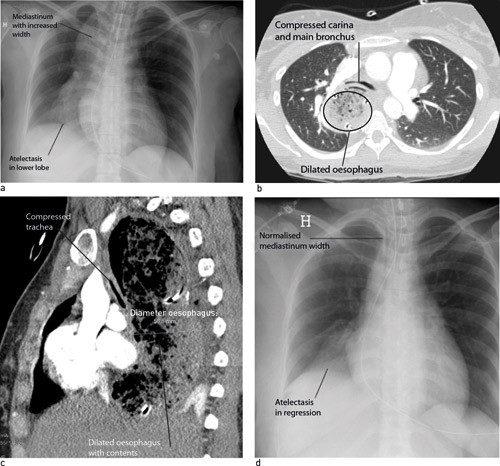

A 34 year old woman was admitted to Rikshospitalet to give birth. For the three previous years she had had increasing dysphagia to fluids and solids, dyspnoea in connection with meals and difficulty in achieving eructation (belching). The birth was uncomplicated, but two days post partum she developed acute respiratory distress after breakfast and had to be intubated. Chest X-ray thorax anterior showed increased upper mediastinum width and right-side lower lobe atelectasis (Fig. 1a). A further assessment with CT thorax showed that the whole oesophagus was considerably dilated and that it was compressing both the trachea and the right main bronchus (Figs 1b, 1c).

Gastroscopy showed a dilated oesophagus with food residue, but no strictures or mucous membrane changes. The lower oesophagal sphincter was immediately dilated with a balloon, on suspicion of achalasia. A control X-ray the same evening showed normalised mediastinum width and partial regression of the lower lobe atelectasis (Fig. 1d). A check-up two weeks later showed the patient to be free of symptoms, and oesophageal manometry showed findings consistent with achalasia.